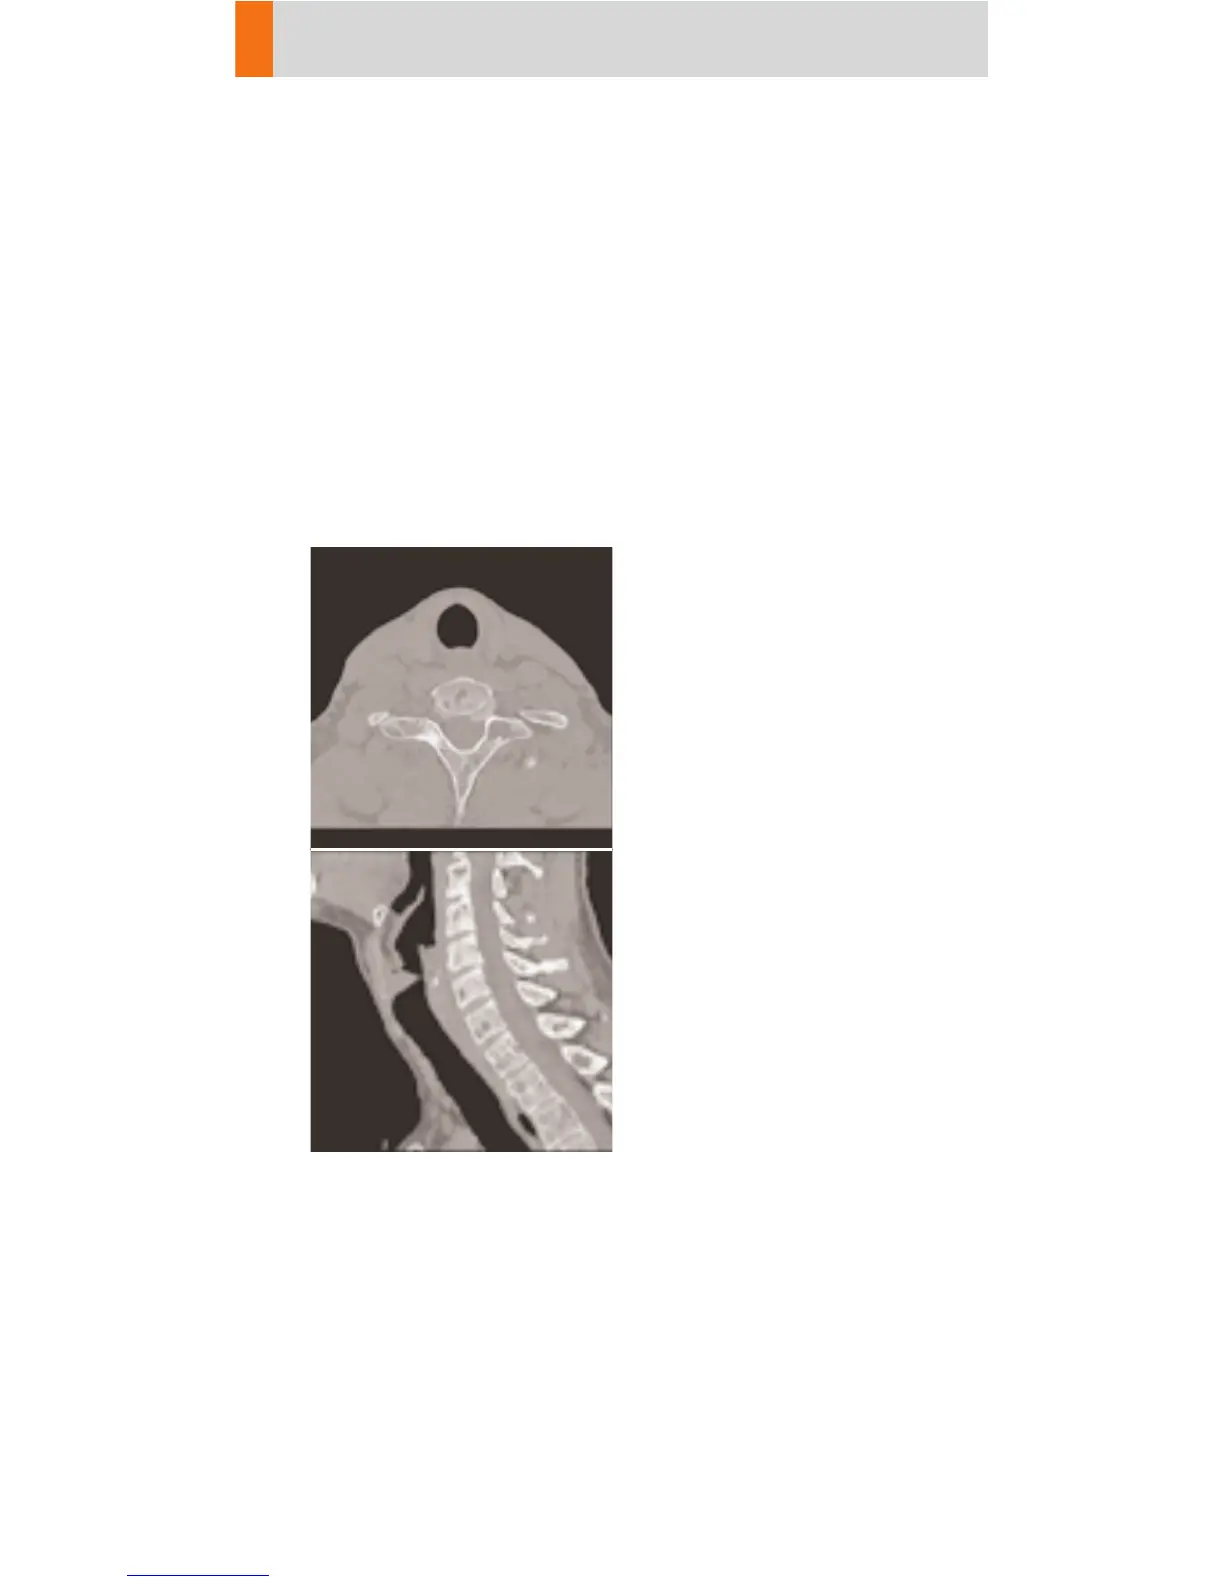

Neck

NeckThinSlice

Spiral mode using thin slices for soft tissue studies.

E. g. the functional study of the throat.

Two recon jobs are predefined: thinner slice recon-

struction used for post-processing, and thicker slice

reconstruction for soft tissue.

A typical range of 20 cm will be covered in 28.3 sec.